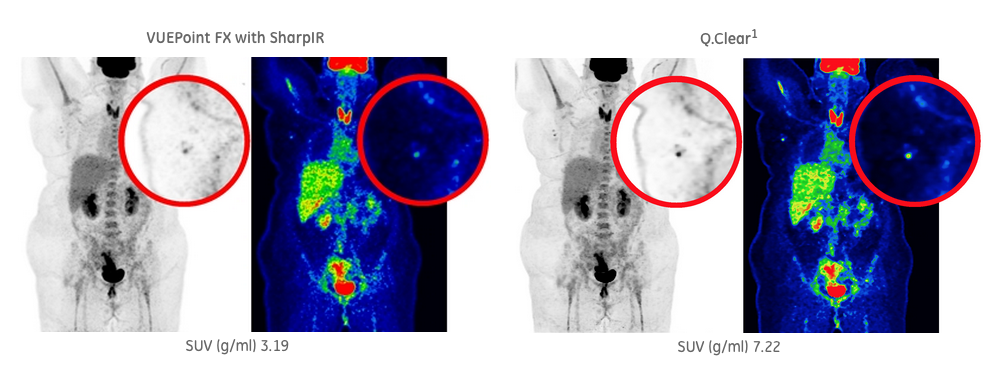

健康・医学 PET in Clinical Oncology PET predicts survival in patients with brain tumors | AuntMinnieの詳細情報

PET predicts survival in patients with brain tumors | AuntMinnie。Next-level theranostics with total-body PET/CT - Siemens。PET Imaging in Clinical Oncology | SpringerLink。PETによるがん診断の専門書で、詳細な技術情報を提供。イラストで理解する呼吸器外科手術のエッセンス。。Frontiers | Clinical advancement of precision theranostics。- タイトル: PET in Clinical Oncology- 著者: Helmut J. Wieler, R. Edward Coleman- ISBN: 978-3-7985-1219-1- 出版社: Springer- 言語: 英語- 内容: PETによるがんの診断と治療に関する詳細な情報を提供する専門書。ご覧いただきありがとうございます。総合内科病棟マニュアル 疾患ごとの管理